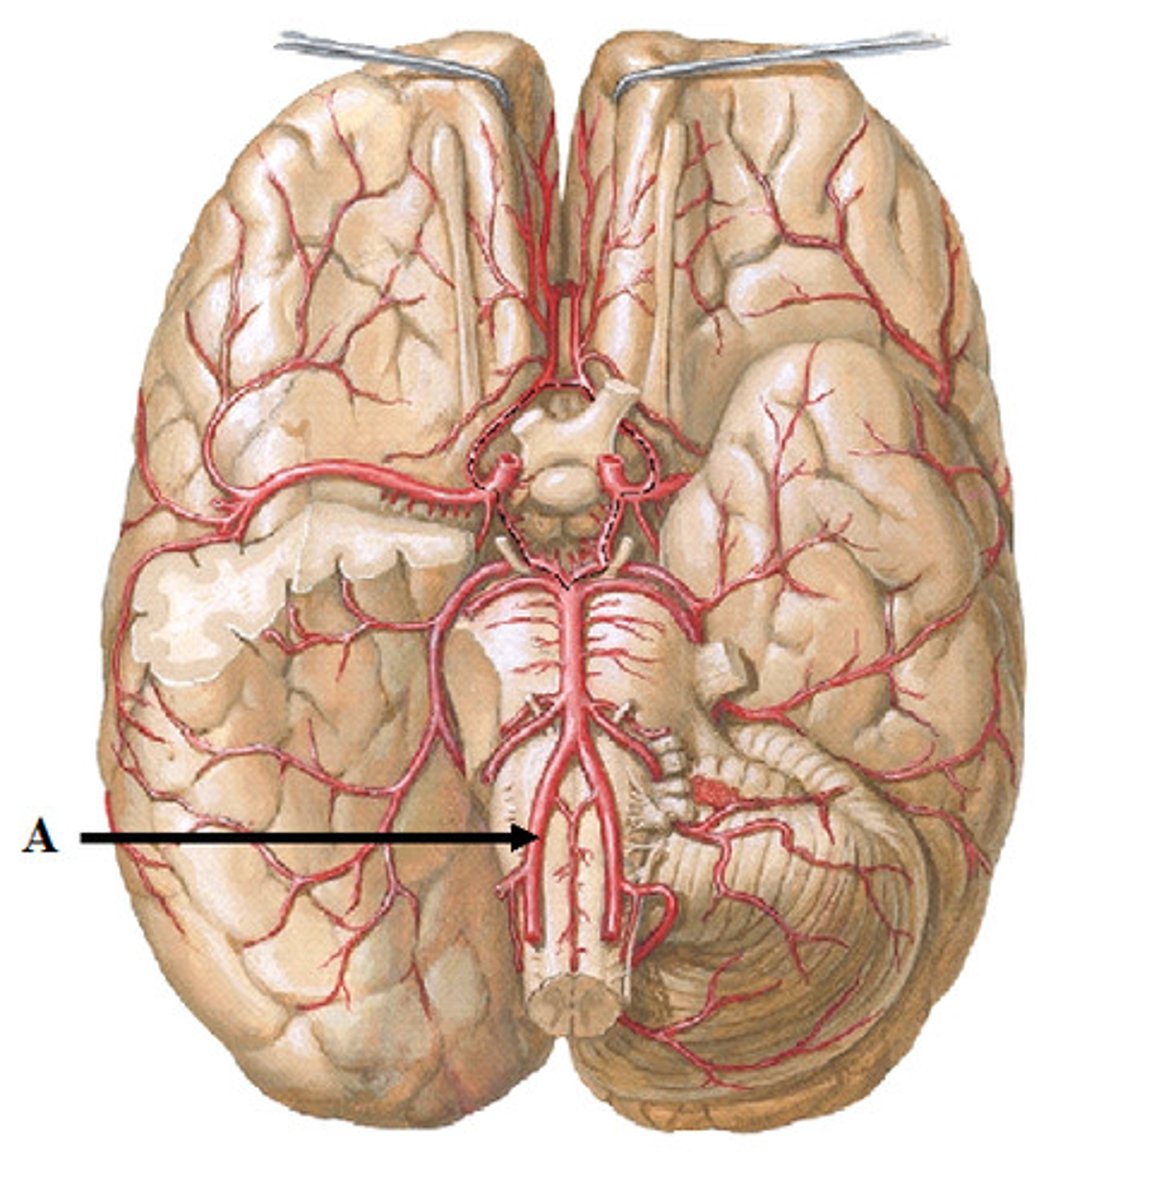

vertebral arteries

Arteries that ascend the vertebrae, enter the base of the skull, and join together to form the basilar artery. Travel through foramen magnum to reach the pons.

internal carotid arteries

this artery branches off the common carotid arteries, travel up into the skull through the carotid canal, and then divide to form the anterior and middle cerebral arteries.

anterior cerebral arteries

two large arteries, arising from the internal carotid arteries. Travels anteromedially to the median longitudinal fissure where it supplies the superior and medial aspects of the frontal and parietal lobes.

middle cerebral arteries

two large arteries, arising from the internal carotid arteries. Dives into the lateral fissure to travel to the lateral aspect of the brain, where it supplies the majority of the temporal lobe and a large portion of the frontal and parietal lobes.

posterior cerebral arteries

Two large arteries, arising from the basilar artery, that supply the posterior aspect of the brain, including the occipital lobes, as well as the inferior portion of the temporal lobes.

anterior communicating artery

Connects the two anterior cerebral arteries before they enter the median longitudinal fissure

posterior communicating artery

small arteries that connect the posterior cerebral and internal carotid arteries.

basilar artery

arises from the vertebral arteries and runs along the pons before dividing into posterior cerebral arteries.